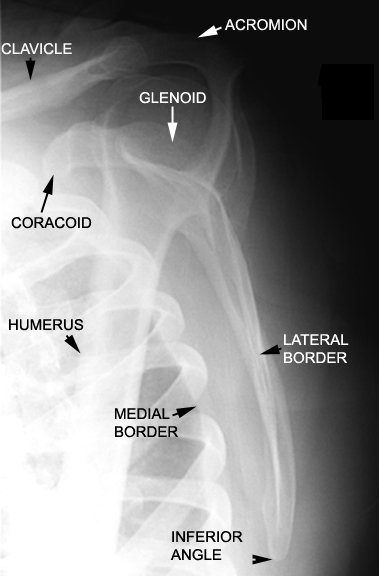

Identify parts of the scapula. Click the image for labeling.